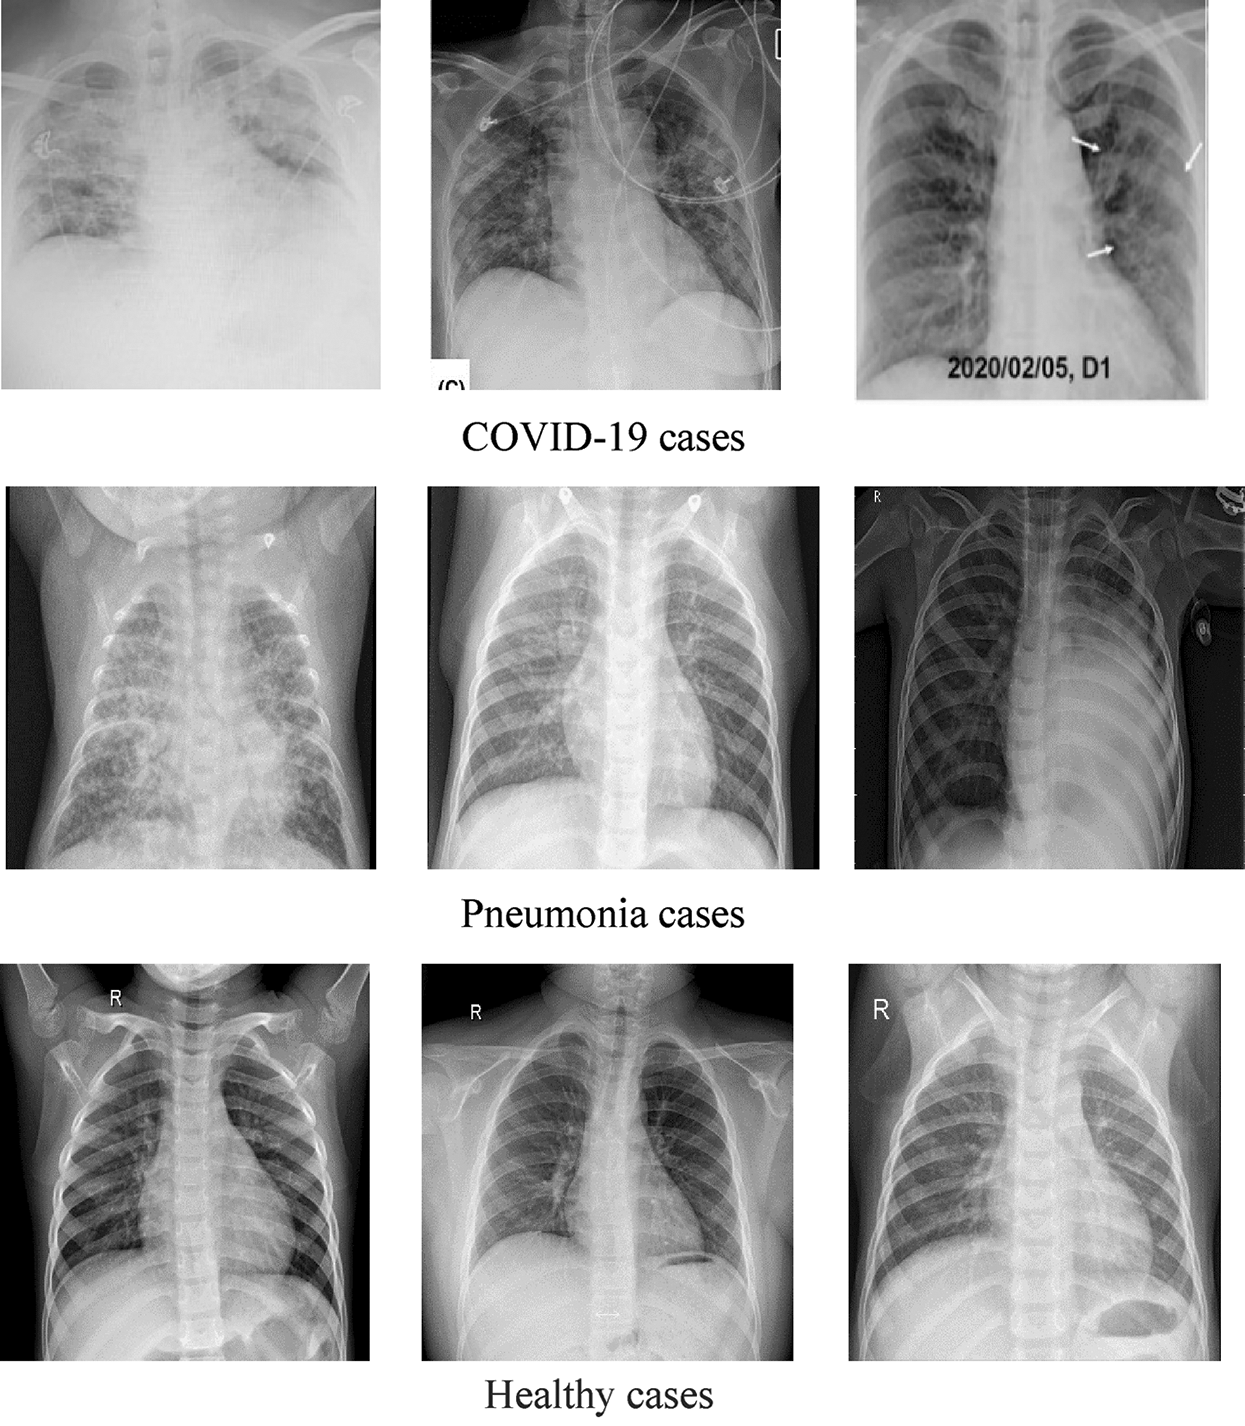

DATASET-1 [35] comprises post-to-antheral chest X-ray (CXR) images as this vision is commonly used in pneumonia diagnosis by radiologists. DATASET-1 comprises four subdatasets; two subdatasets were constructed by the authors, and the other two were collected from two repositories, Kaggle and GitHub, which are publicly accessible. The first subdataset is collected from the “Italian Society of Medical and Interventional Radiology (SIRM) COVID-19 DATABASE” and comprises 330 positive COVID-19 radiography CT and CXR images with different resolutions, where 70 images are CXR and 250 images are CT images of the lung. The second subdataset is collected from “Novel Corona Virus 2019 Dataset” and comprises 179 radiography images of COVID-19, Middle East respiratory syndrome, severe acute respiratory syndrome, and ARDS from written papers and web resources, created by Lan Dao, Joseph Paul Cohen, and Paul Morrison in GitHub46. The third subdataset is collected from “COVID-19 positive CXR images from different articles.” Datasets collected from GitHub have motivated researchers to study the literature, and as a result, in less than two months, more than 1200 articles were published. The fourth subdataset is a Kaggle CXR dataset, comprising 5247 CXR images with resolutions ranging from 400 to 2,000 pixels for regular, viral, and bacterial pneumonia. Of these, 3,906 are pneumonia-affected pictures from multiple subjects (25,561 bacterial pneumonia pictures and 1,345 virus pneumonia pictures) and 1,341 are from healthy subjects. Fig. 1 illustrates some samples of DATASET-2.

Figure 1: Sample X-ray images from DATASET-1 showing COVID-19, viral pneumonia, and healthy cases